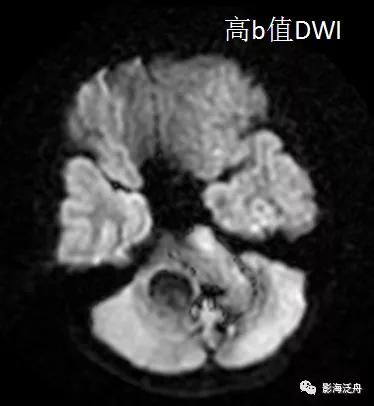

上图可见右侧桥臂一类圆形异常信号,T1WI呈中央稍低信号,边缘环形高信号,T2WI以低信号为主,局部可见液液分层(红箭),高、低b值DWI显示病变区域信号丢失。通过上述信号改变,不难看出是一个急性期血肿(血肿分期详见 MR上脑出血信号的演变机制)。

诊断虽然明确了,但故事到这里还没结束,回过头去看患者第一次检查的低b值DWI序列,可以发现这些病灶其实早就存在。但为什么第一次检查的时候没有及时发现呢?想必这大概率是因为大家对低b值DWI序列认识不足造成的,尤其是低年资诊断医生和神经科临床医生往往会自动忽略掉低b值DWI序列,再或者就是把低b值DWI误认为是高b值DWI序列。

在低b值DWI序列可以看到左侧大脑半球多发磁敏感伪影(红箭)。

从理论上讲,无论高b值DWI还是低b值DWI序列都应该对磁敏感伪影很敏感,但实际情况是不是这样呢?看下图↓↓

上图可以发现,在低b值DWI序列上左侧额顶叶交界区的病灶显示清晰(红箭),但在高b值DWI序列上,除病灶外,多个脑沟也表现出磁敏感伪影(绿箭)。因此,当病灶足够小或者数量比较少的时候很难区分到底是伪影还是病灶,而低b值DWI序列可以较好地解决这一问题。